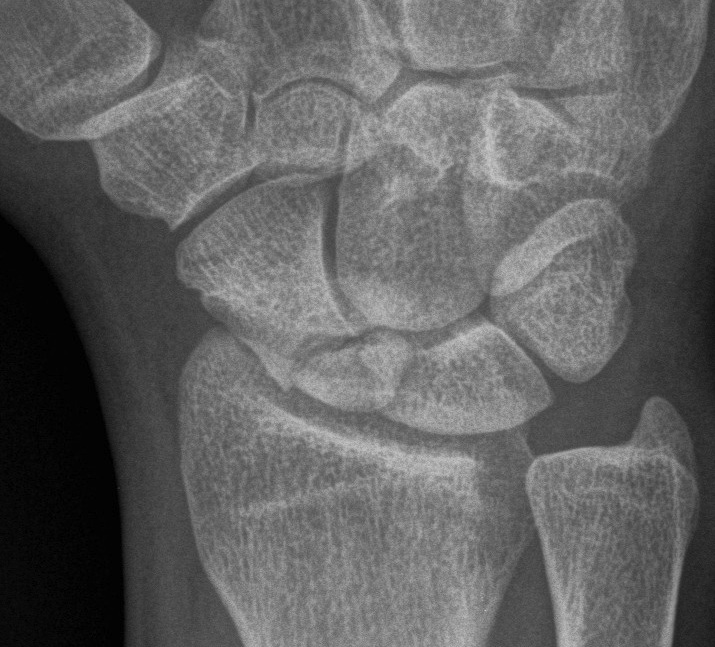

X-ray

5 images

- PA / lateral

- PA in 45° oblique pronation / PA 45o oblique supination

- PA in ulna deviation

Occult scaphoid fracture

Issue

Tender in anatomical snuffbox with normal xrays

Occult fracture on delayed xrays / CT / MRI